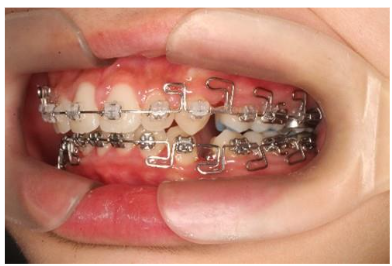

The arch continuity remains intact as the bracket can be placed on the targeted extraction tooth.

Figures 7, 8, and 9 show the differences between the non-extraction case, extraction using a straight wire without precautions when closing the extraction gap, which causes bowing, and the Root Canal Before Extraction method, which provides space even when the bicuspid has not been removed. The spaces were created using interproximal reduction. The MEAW closing loops for final alignment were activated immediately after extraction.